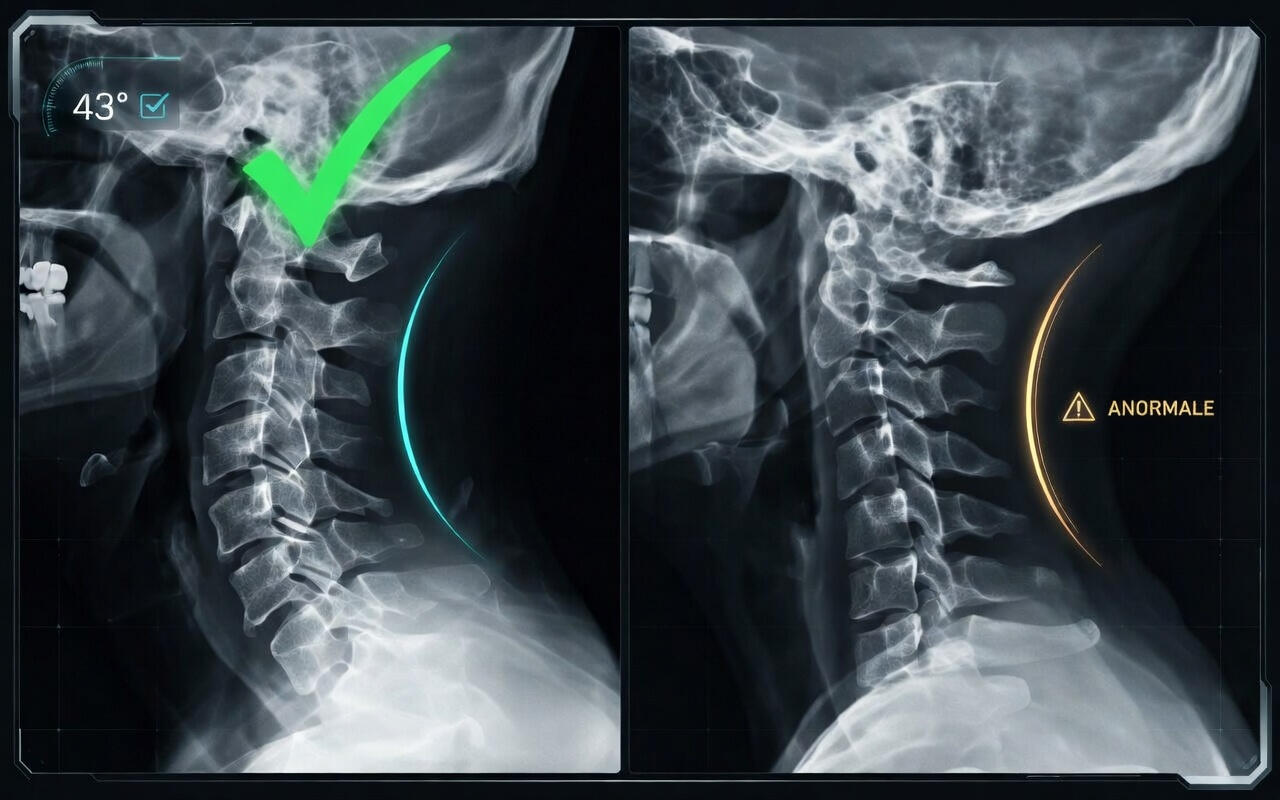

Il tuo collo ha perso la sua curva naturale

La curva cervicale si appiattisce. Le vertebre si comprimono. I nervi vengono schiacciati.